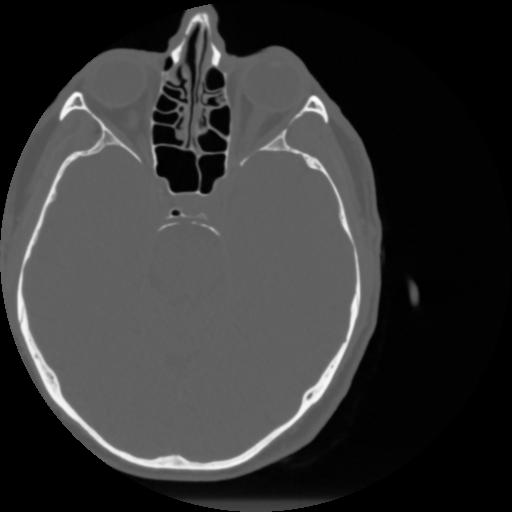

4 CEREBRO,,Vol,0.5,CEREBRO,,